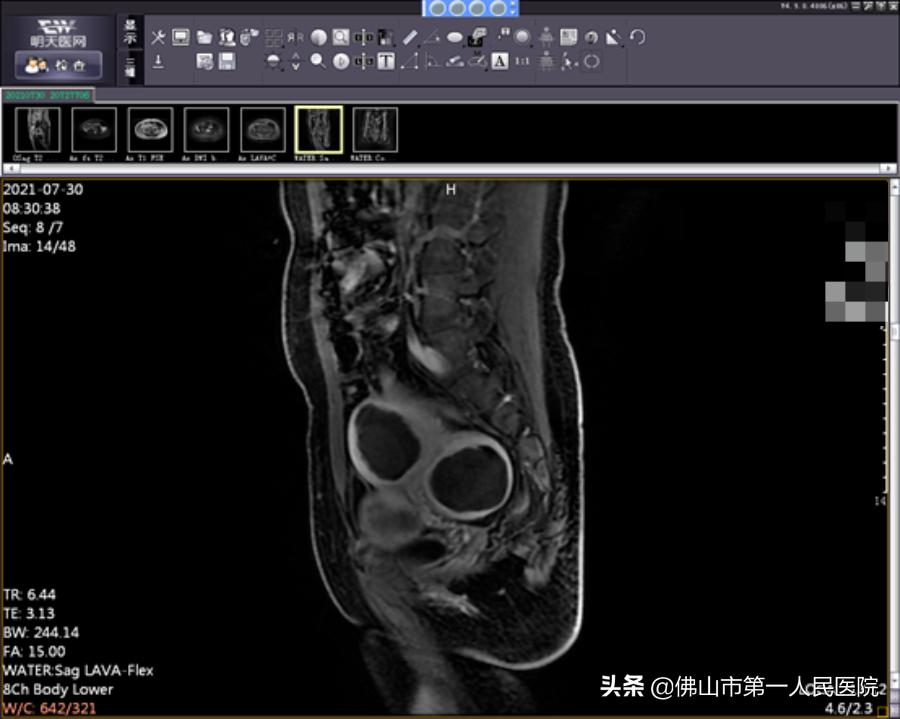

术前图像

经充分检查和术前评估,陆女士符合“海扶刀”治疗指征。由于陆女士子宫肌瘤分布于于肌壁间、黏膜下和浆膜下,数量较多,大小不一,我院海扶中心潘智茵副主任及其团队结合多年“海扶刀”治疗经验,制定了宫腔镜检查联合“海扶刀”手术的治疗方案。

2021年7月,医生为陆女士行宫腔镜检查,子宫内膜未见明显异常,粘膜下肌瘤向宫腔凸起小于二分之一,大于二分之一位于肌壁间。宫腔镜检查术后1天患者无明显阴道流血,遂行海扶刀手术。